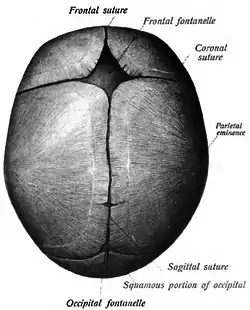

![]() Human adult skull from above. | |

The sagittal suture, also known as the interparietal suture and the sutura interparietalis, is a dense, fibrous connective tissue joint between the two parietal bones of the skull. The term is derived from the Latin word sagitta, meaning arrow.

The sagittal suture is formed from the fibrous connective tissue joint between the two parietal bones of the skull.[1] It has a varied and irregular shape which arises during development.[1] The pattern is different between the inside and the outside.[1]

Two anatomical landmarks are found on the sagittal suture: the bregma, and the vertex of the skull. The bregma is formed by the intersection of the sagittal and coronal sutures. The vertex is the highest point on the skull and is often near the midpoint of the sagittal suture.